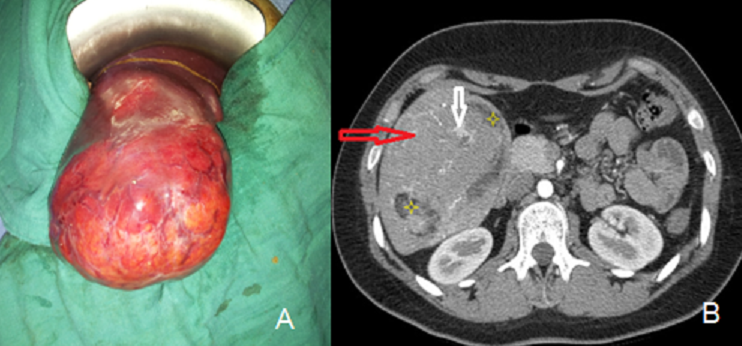

L'angiomyolipome est une tumeur bénigne mésenchymateuse exceptionnelle du foie. Il existe une prédominance féminine (sexe ratio : 2,5/3) avec un âge moyen lors du diagnostic de 50 ans. La localisation hépatique droite est classique. La taille est extrêmement variable allant de 1 cm à plusieurs dizaine de cm. La possibilité de complication hémorragique est réelle notamment pour les tumeurs volumineuses. L'association d'une sclérose tubéreuse de Bournonville, communément admise pour la localisation rénale, est rare pour l'angiomyolipome hépatique (4-6%) . Nous rapportons l'observation d'une patiente âgée de 19 ans, qui présente depuis 4 mois des douleurs de l'hypochondre droit à type de pesanteur, évoluant dans un contexte de conservation de l'état général. L'examen clinque objective une énorme masse du l'hypochondre droit débordant au niveau flanc droit. Par ailleurs, il n'existe ni ictère ni d'autres signes associés. Un bilan biologique comportant les enzymes de cytolyse/cholestase, les sérologies hépatitiques et les marqueurs tumoraux (Alpha FP, CA 19-9, ACE) est strictement normal. Un scanner abdominal avait mis en évidence une volumineuse formation tissulaire, de 12 cm au dépend des segments 5 et 6 hépatiques à développement exophytique. Cette formation, bien limitée, comporte également des composantes graisseuses et vasculaires. Le diagnostic d'angiomyolipome est fortement suspecté, sans par ailleurs exclure le diagnostic de CHC sur foie sain ou d'adénome atypique. La résection de la tumeur a été conduite par voie sous costale droite ; Les suites opératoires immédiates étaient simples. L'examen anatomopathologique de la pièce opératoire confirme le diagnostic d'angiomyolipome hépatique : prolifération tumorale à triple composante adipeuse, tissulaire et vasculaires, exprimant la HDM 45 et l'actine musculaire lisse. Le suivi en consultation, après trois mois de l'intervention, est sans particularités ; l'examen dermatologique est normal, excluant l'éventualité d'une association à la sclérose tubéreuse de Bournonville. A long terme, aucune surveillance n'est requise compte tenu du caractère strictement bénin de cette tumeur.